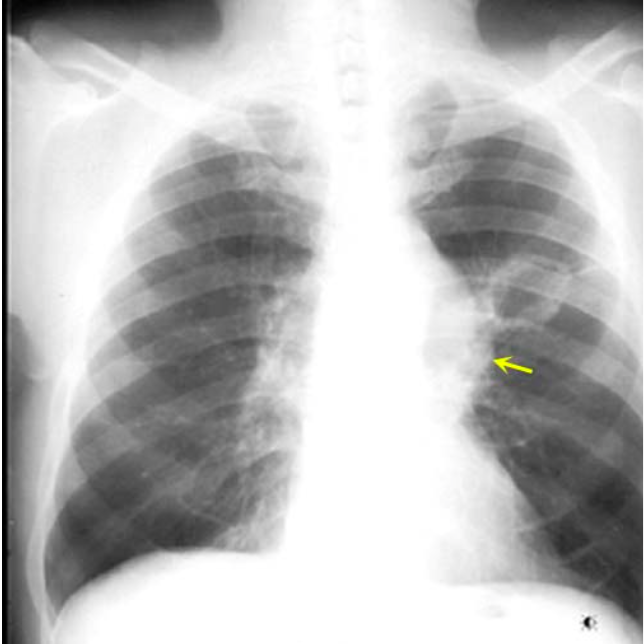

What is shown in the image?

Cavitating Squamous Cell Cancer